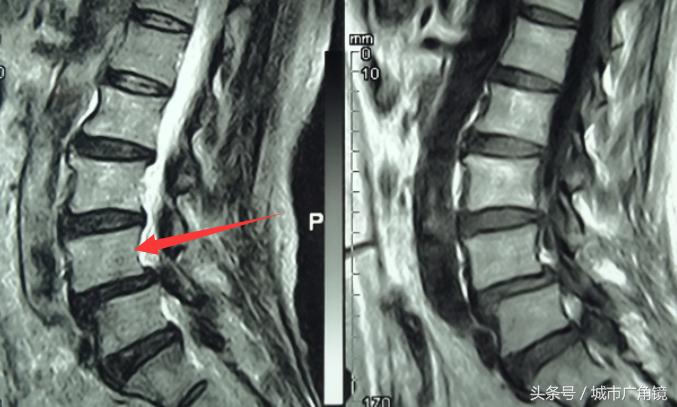

▲椎体滑脱

然而,根据光学影像资料显示,杨大娘除椎管狭窄外,其腰4椎体还同时存在滑脱的问题。对此,医生同样给予患者耐心解释:椎体滑脱主要由椎间盘退变、周围韧带松弛、椎间隙不稳等引起。简单来讲,就是某个椎体相对于其相邻的椎体产生了前后滑移,刺激或压迫到神经根,进而产生腰腿痛。